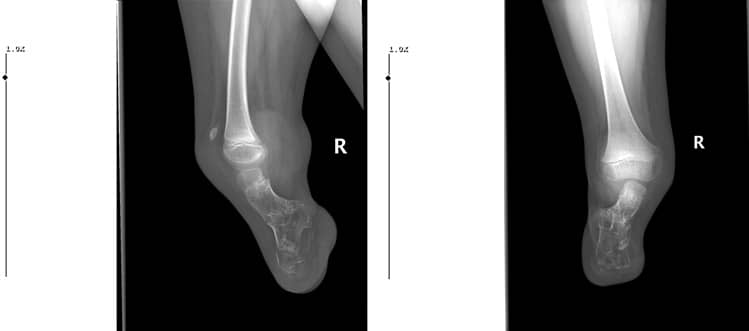

Когато пациентът дойде при нас за контрол осем години по-късно, беше установено, че изпитва болка поради костно израстъче в задно-страничната част на крузиса, валгусна деформация и липса на приблизително 25-градусово разгъване в коляното (Фиг. 7. А, В.).

Фиг. 7: А: Сагитален изглед

B: Коронален изглед

Обхватът на сгъване беше почти пълен. В резултат на това беше препоръчана операция за корекция на механичната ос, за да се постигне почти пълно разгъване на коляното и за отстраняване на костното израстъче, което притиска протезата. Планирана беше отворена клиновидна остеотомия с цел предотвратяване на скъсяване на остатъка на крузиса, според рентгеновото изследване на пациента.

Преоперативни изображения, показващи валгусната и флексионната деформации на засегнатия крак (Фиг. 8 А, В).

Фиг. 8: Преоперативни изображения, показващи

А. Валгусна деформация

В. 25-градусова контрактура на флексият